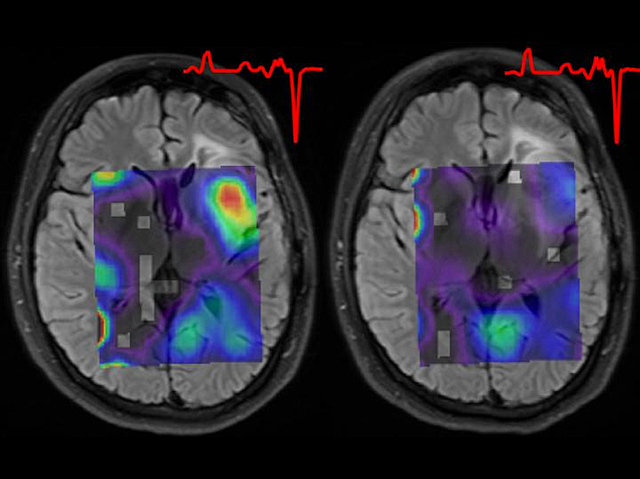

Tracking Tumours

Tracking animals through a forest, the footprints and droppings they leave behind reveal their size, health and habits. And for doctors hunting tumours in the body, the molecules and materials they produce provide important clues. For example, assessing gliomas – deadly brain tumours – is tricky, so a new approach is using magnetic resonance spectroscopy to visualise their metabolic, rather than structural, properties. By revealing the presence of a substance often produced by tumours, the scans can monitor its activity and response to treatments. For example, after just one week of an experimental treatment, the amount of 2HG – a molecule known to initiate and boost tumour growth, orange in these brain scans – produced by a patient’s glioma was dramatically reduced (right). Similar scans also showed reductions in other tumour outputs, suggesting the treatment is reprogramming its activity, and highlighting the value of this new tracking tool in the tumour hunter’s arsenal.